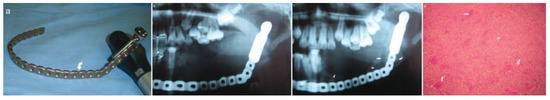

The ECA was identified and ligated (Figure 3a). The tumor was then dissected subperiosteally and resected, followed by immediate reconstruction using a titanium heavy reconstruction plate (Figure 3b). The tumor mass was removed via an intraoral approach. Postoperative recovery was un-eventful. The biopsy report confirmed the lesion as being an ABC (Figure 4d). Due to the long span of the defect, it was envisaged that a delayed free fibula reconstruction be done subsequently.

Figure 3. (a) Approach to external carotid artery. (b) Reconstruction plate after fixation. (c) Resected specimen. (d) Stereolithographic model.

Figure 4. (a) Prebent reconstruction plate. (b) One-week postoperative orthopantomograph. (c) Eighteenth-month postoperative orthopantomograph showing evidence of osteogenesis (arrows). (d) Micrograph showing multinucleated giant cells (arrows).

The surgical wounds healed without complications. Review of the patient after 18 months showed no recurrence of the lesion. New bone formation was clinically palpable and evident on radiographs (Figure 4c), which negated the need for grafting. Depending on patient compliance and financial affordability, long-term follow-up visits are planned with a view to obtaining CT scans to assess the degree of new bone formation with histology, temporomandibular joint function and growth.